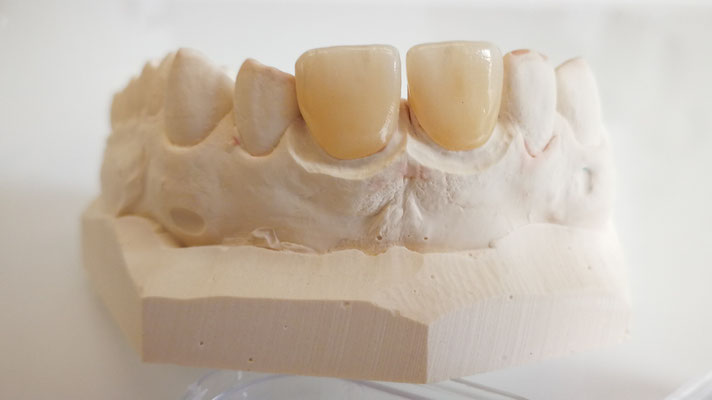

Keramikrestaurationen

Grössere Defekte der Zahnhartsubstanz werden idealerweise in Keramik restauriert. Meist wird das Werkstück von einer Fräsmaschine (CAD; computer-aided

design) aus einem Keramikblock gefräst.

So können grosse Füllungen (Inlay, Onlay, Overlay), Veneers (Verblendschalen) mit höchster Passgenauigkeit und Stabilität hergestellt werden. Nach dem Fräsen wird das Keramikwerkstück mit einem Kompositzement in / auf den Zahn geklebt (einzementiert).